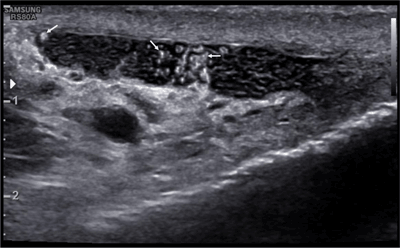

Figure 2

Irregularly shaped, hyperechoic particles (arrows) within the cystic dilatations of the epididymis.